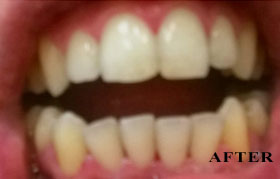

PHOTO GALLERY

Cosmetic, Reconstructive & Athletic Dental Surgeon - Smile Design / Implants